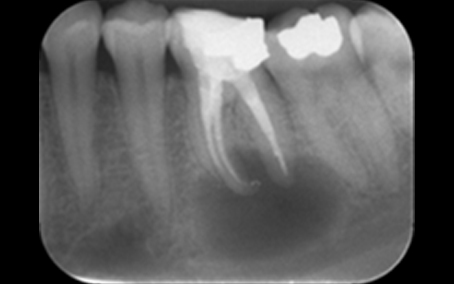

Radiograph 1 2018

Radiograph 1 2023